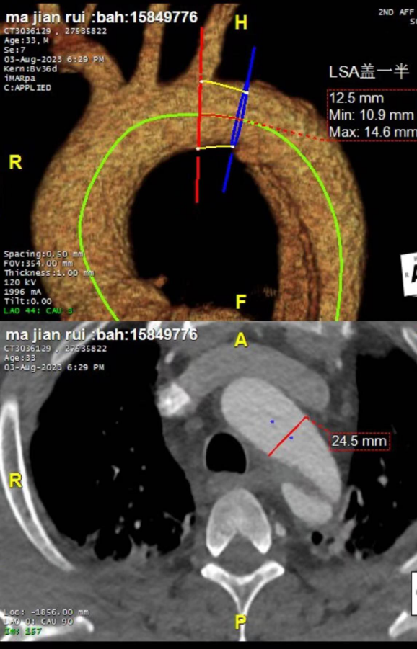

患者很年轻,不希望支架开窗或干扰左锁骨下动脉,但破口紧邻左锁骨下动脉小弯侧(小弯侧破口距锁骨下动脉只有7mm,大弯侧9mm),挑战比较大。需要评估是否延长近端锚定区以覆盖病变,同时避免影响重要分支血供。

③ 支架选择策略:通过术前规划模拟不同口径、长度支架的植入效果,预测术后真腔重塑及对血流动力学(如压力梯度、远端供血)的影响,最终选择适配血管直径及病变范围的支架。

根据体外模拟演示和临床可选择支架情况,判定28mm支架对真腔重塑,远端血流动力学恢复效果最佳,决定植入直径28mm,长度160mm胸主动脉支架